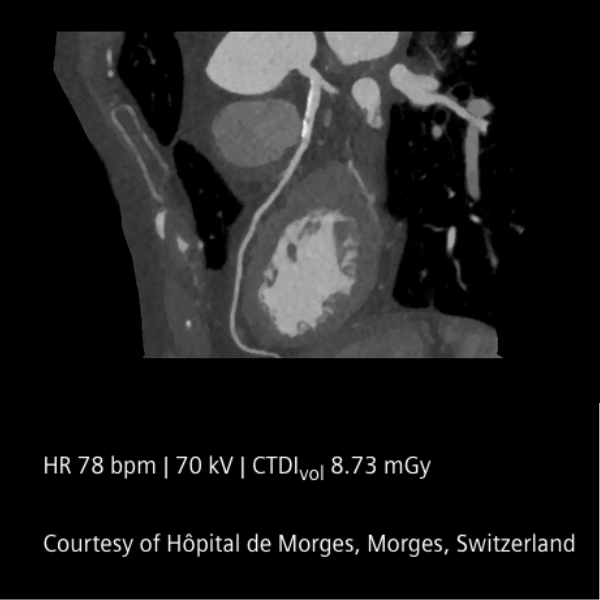

En el corazón del sistema se encuentran los detectores QuantaMax, capaces de medir cada fotón individualmente y convertirlo directamente en señal eléctrica. Esto permite eliminar el ruido electrónico, mejorar la relación contraste/ruido y obtener imágenes de alta resolución espectral sin aumentar la dosis de radiación. La combinación con la tecnología Dual Source y el potente tubo Vectron X-ray garantiza un rendimiento excepcional incluso en pacientes con alto índice de masa corporal.

El NAEOTOM Alpha ofrece velocidades de escaneo ultrarrápidas y una resolución temporal nativa de 66 ms, ampliando las posibilidades clínicas en cardiología, oncología, neurología y estudios complejos. Sus flujos de trabajo asistidos por inteligencia artificial optimizan la operación y apoyan la toma de decisiones clínicas.